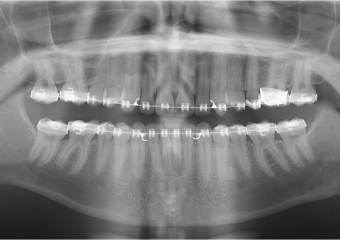

Raio x inicial